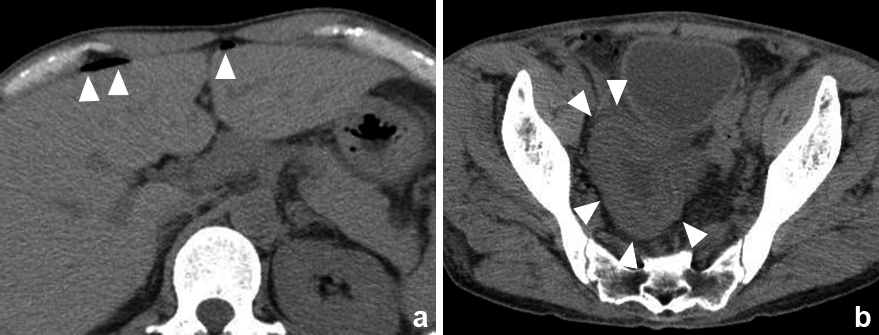

腹部CT所見:骨盤内に限局した小腸の浮腫を認め,その周囲に少量の腹水貯留を認めた.骨盤内と肝表面にfree airを認めた(Fig. 1).

Preoperative CT findings. a. Free air on the surface of the liver (arrowheads). b. Edematous small intestine in the pelvis (arrowheads).